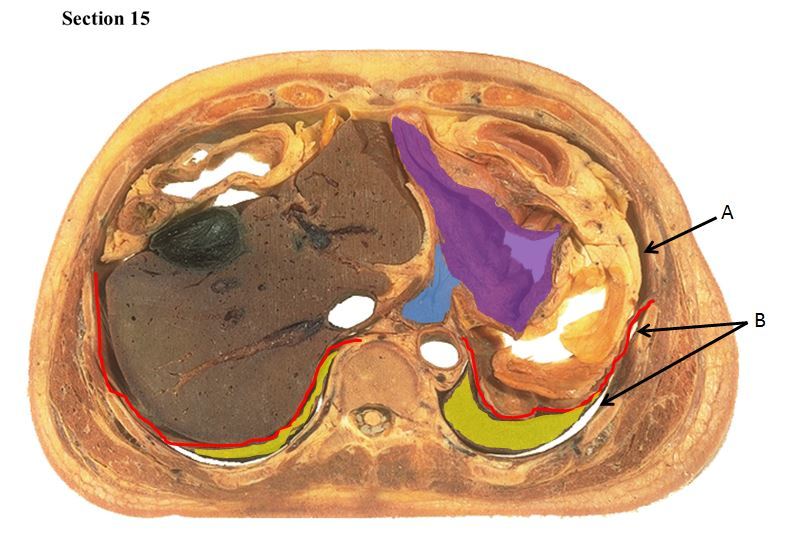

15

The red muscle is the _____

The orange organ is the _____

A

diaphragm

liver

16

The blue organ is the _____ and the yellow organ is the _____.

The purple structure is the _____

right lung

left lung

esophagus

17

The red line is a muscle called the ___ which separates cavity A called the ___ from cavity B which is called the ___

peritoneal cavity

pleural cavity

18

Q

In cavity A, the blue organ is the ___ and it deposits materials into the purple organ which is the ___

stomach